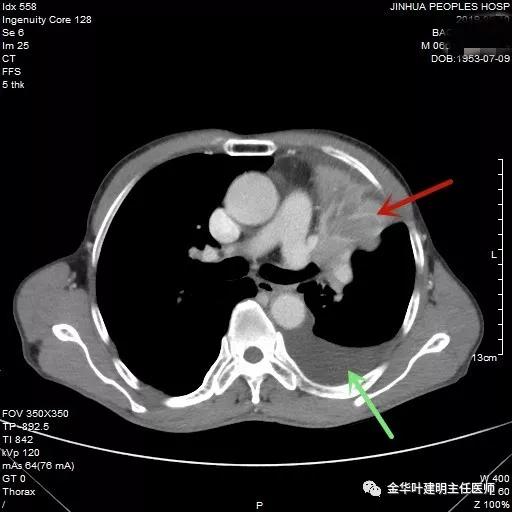

红色箭头示不张的肺,绿色示胸水

肿瘤与左肺动脉主干关系密切